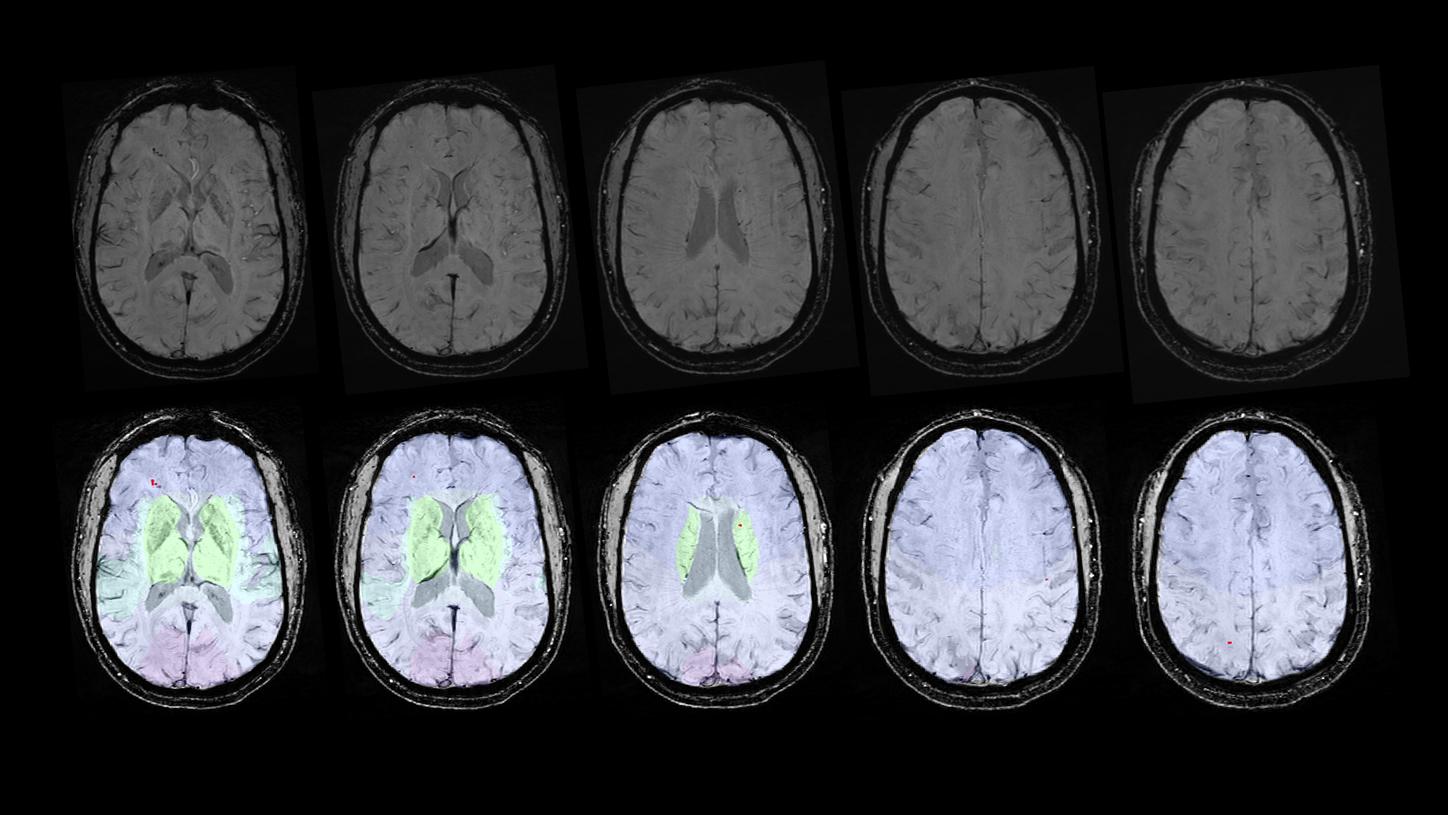

MR-Bilder Amyloid-bedingter Bildgebungsanomalien (ARIA-H und ARIA-E). Dies sind mögliche unerwünschte Nebenwirkungen der neuen krankheitsmodifizierenden Alzheimer-Therapien.4

KI-gestützte Erkennung zerebraler Mikroblutungen (Prototyp).

4 Diese Anwendung ist nur für Forschungszwecke bestimmt und darf nicht zur Diagnose einzelner Patient*innen verwendet werden. Die genannte Anwendung ist möglicherweise nicht in allen Ländern verfügbar. Weitere Informationen über diese Forschungsanwendung und ihre Verfügbarkeit in Ihrem Land erhalten Sie von Ihrer Ansprechperson bei Siemens Healthineers.